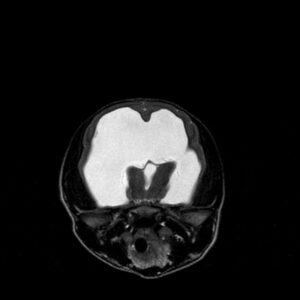

MRI is the most reliable and comprehensive method for diagnosing hydrocephalus. Not only can we see the enlarged ventricles, but we can also see what’s causing it. In some cases, a spinal tap is performed following an MRI to check for infection.